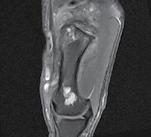

CT-ul cu reconstrucție tridimensională sau RMN genunchi relevă mult mai

bine complexitatea fracturii și dau posibilitatea unui planning preoperator superior estimării radiologice clasice(7). CT-ul este mai rapid și mai ușor de făcut, dar RMN decelează mai bine leziunile de menisc sau ligamentare.